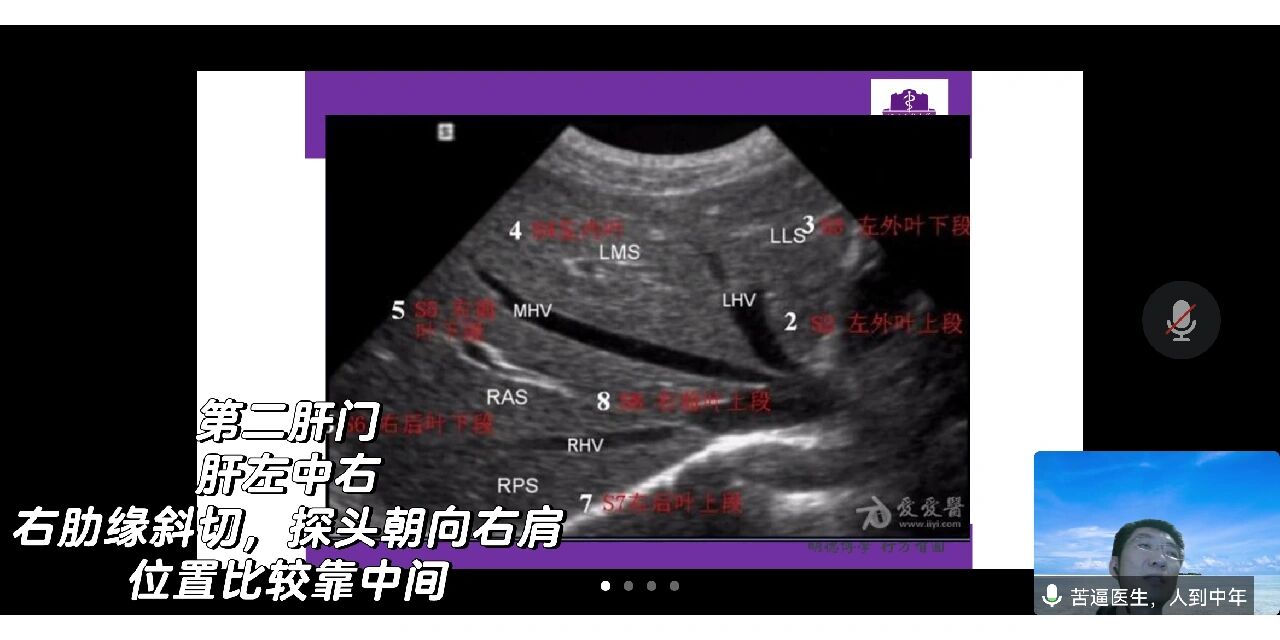

第二肝门超声手法图解

第二肝门

第二肝门横断层面